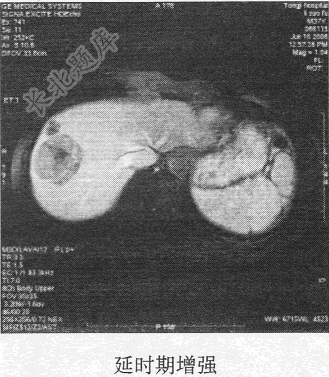

- 单项选择题患者男,54岁。体检发现肝脏占位,MR图像如下,最有可能的诊断是

C、肝血管瘤